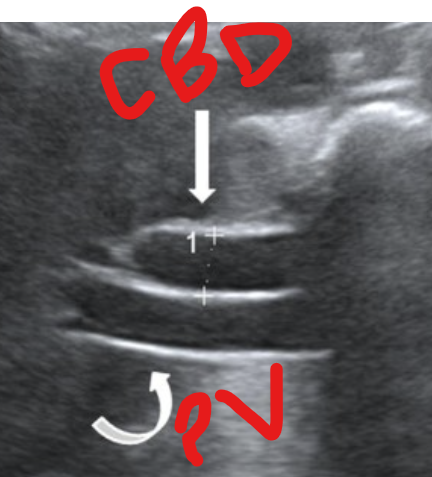

what is the Double Barrel Shotgun Sign?

dilated common bile duct

Portal Vein and Bile Duct near the same size due to dilation of the Bile Duct

See parallel tubular structures in the portal triad with two tubes about the same size.

what is shown?

double barrel shotgun sign